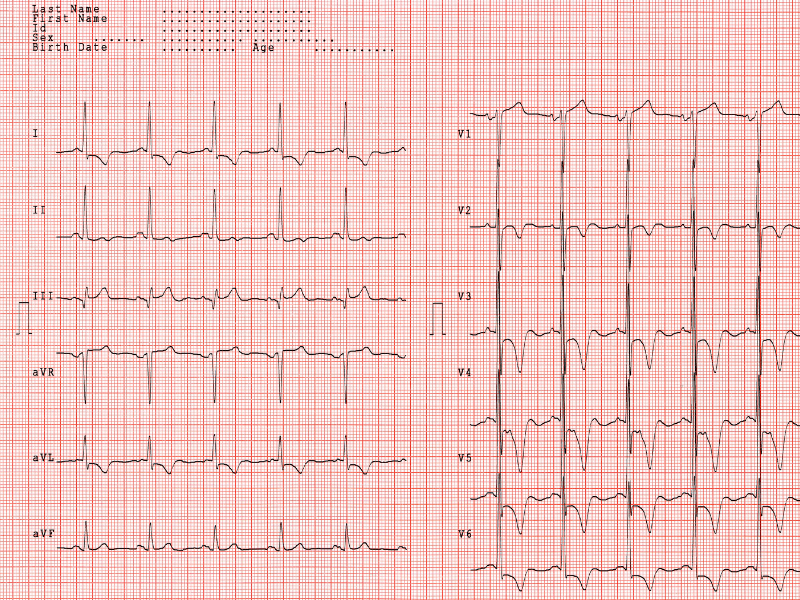

Figura 5: ECG evidenciando sinais de sobrecarga ventricular esquerda, com aumento de amplitude das ondas R e repolarização ventricular com padrão strain.

Figura 5: ECG evidenciando sinais de sobrecarga ventricular esquerda, com aumento de amplitude das ondas R e repolarização ventricular com padrão strain.

Figura 4: Exemplo de bloqueio atrioventricular de segundo grau Mobitz I (Fenômeno de Wenckebach). Observe o aumento progressivo do intervalo PR. Figura 5: ECG evidenciando sinais de sobrecarga ventricular esquerda, com aumento de amplitude das ondas R e repolarização ventricular com padrão strain.

Figura 5: ECG evidenciando sinais de sobrecarga ventricular esquerda, com aumento de amplitude das ondas R e repolarização ventricular com padrão strain. Figura 6: Bloqueio de ramo esquerdo. A definição de bloqueio de ramo envolve a ocorrência de complexos QRS com duração igual ou maior a 120ms e com morfologia indicando acometimento do ramo esquerdo ou direito.